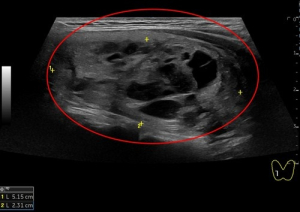

大脖子症怎麼辦?花蓮慈院導入甲狀腺結節消融治療可免開刀

日前,一位51歲女性病人因頸部中間部位腫大來花蓮慈濟醫院影像醫學部施于泰醫師門診,經以超音波檢查,發現右邊有一5.15公分結節,另一個結節靠近甲狀腺峽部約2.99公分;在以細胞學穿刺檢查後為良性結節。病人在接受甲狀腺消融術治療後,隔天即出院恢復正常生活,且一週後已明顯消腫,無副作用發生。